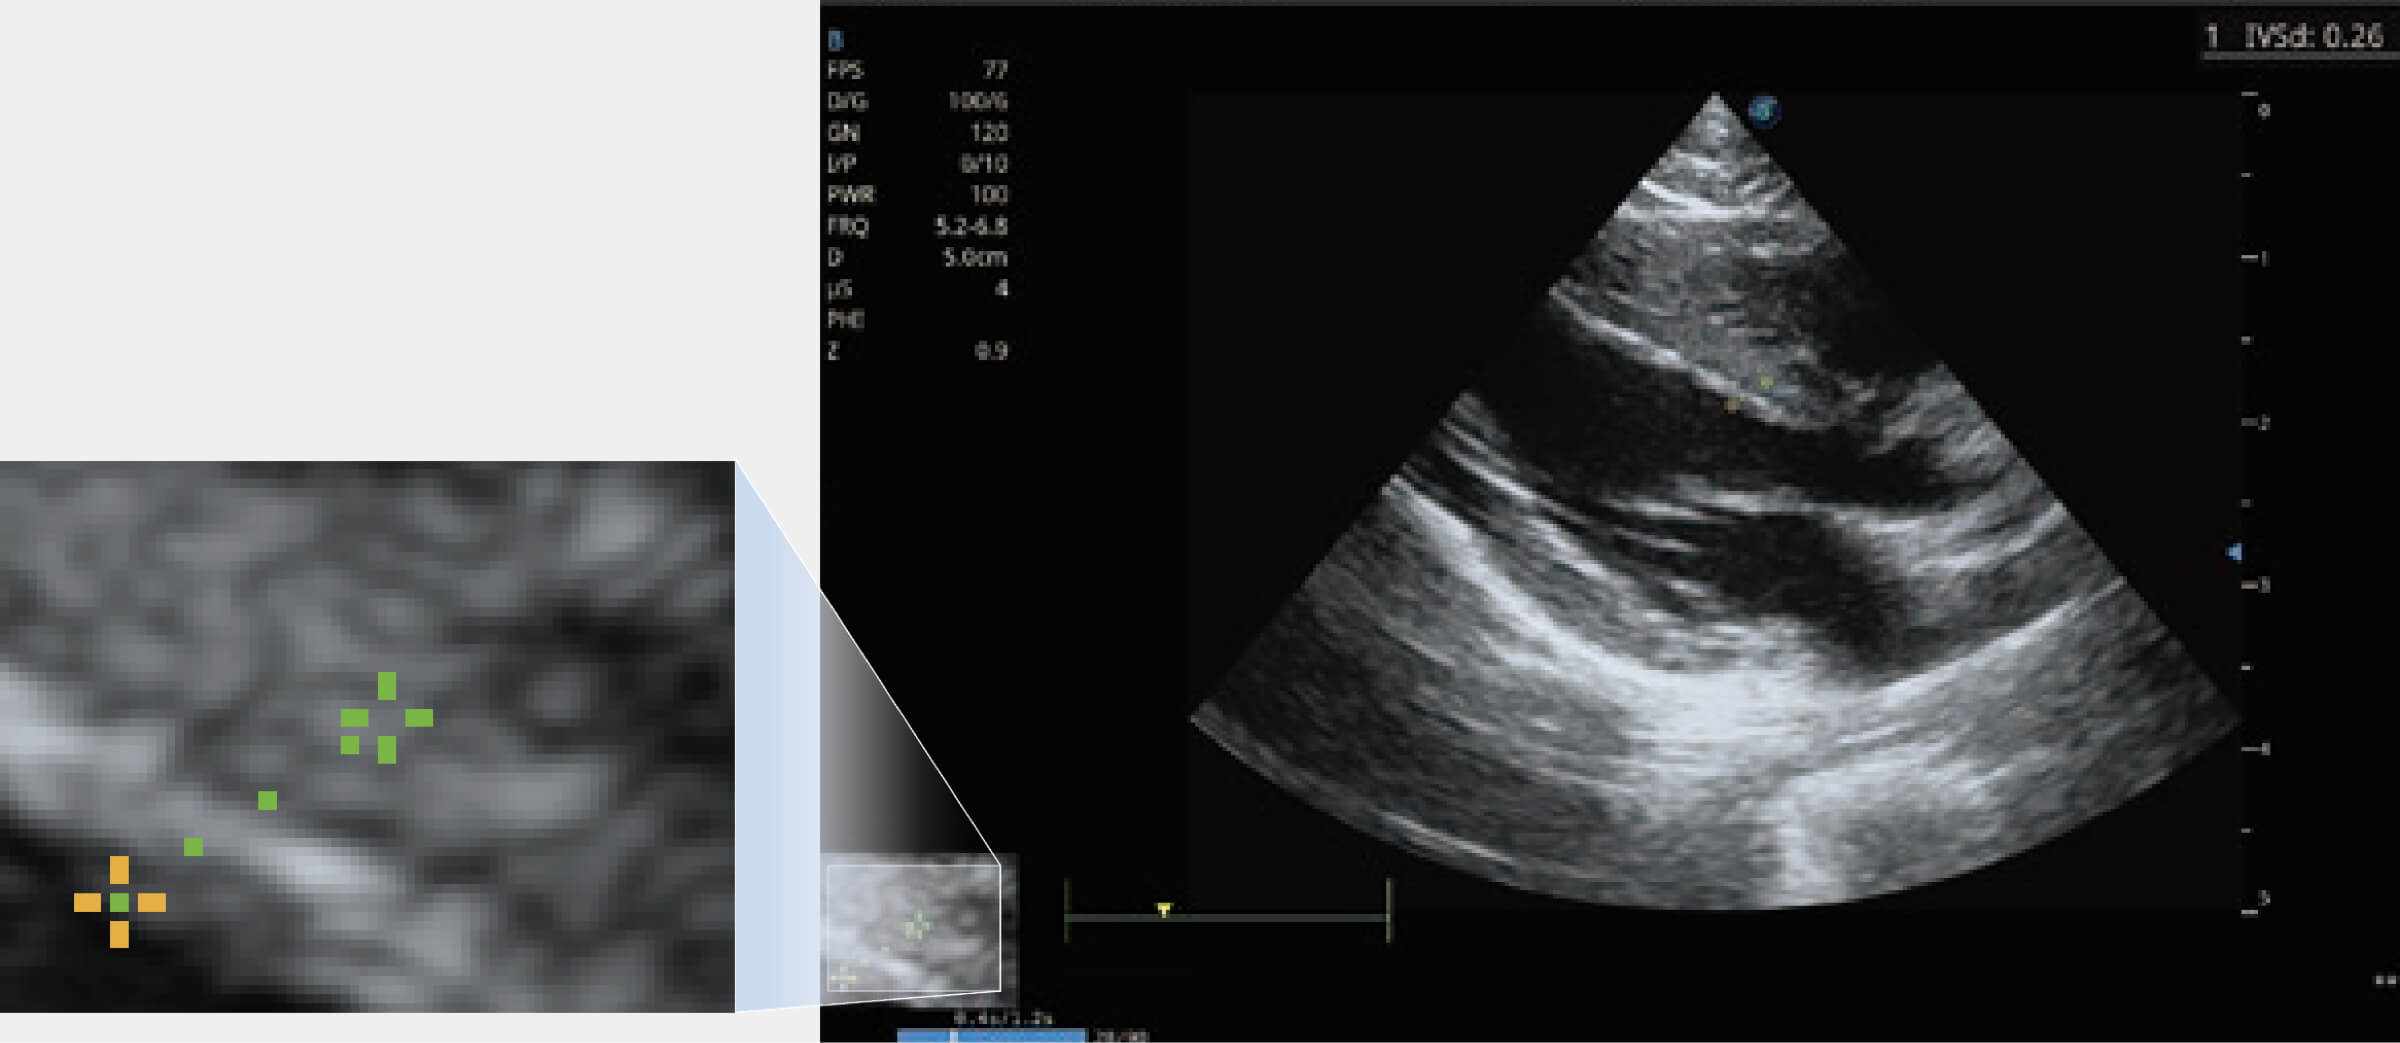

為精細(xì)結(jié)構(gòu)及組織邊緣提供高清晰度的圖像和更大的成像視野。幫助減輕醫(yī)生的用眼疲勞,快速精準(zhǔn)獲得測(cè)量的數(shù)據(jù)。

當(dāng)心臟測(cè)量結(jié)果超出正常范圍時(shí),可實(shí)時(shí)預(yù)警提示動(dòng)物醫(yī)生,減少疾病漏診概率。